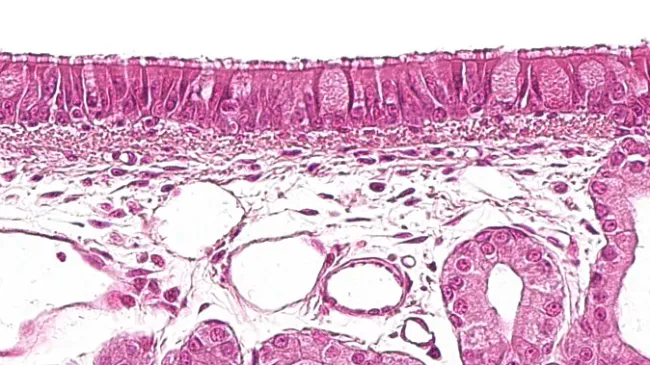

Learn to assess organs and tissues by identifying lesions and abnormalities—focusing on location, shape, color, and more. We'll also explore key areas like the lungs, with real photos to help you differentiate types of pneumonia.